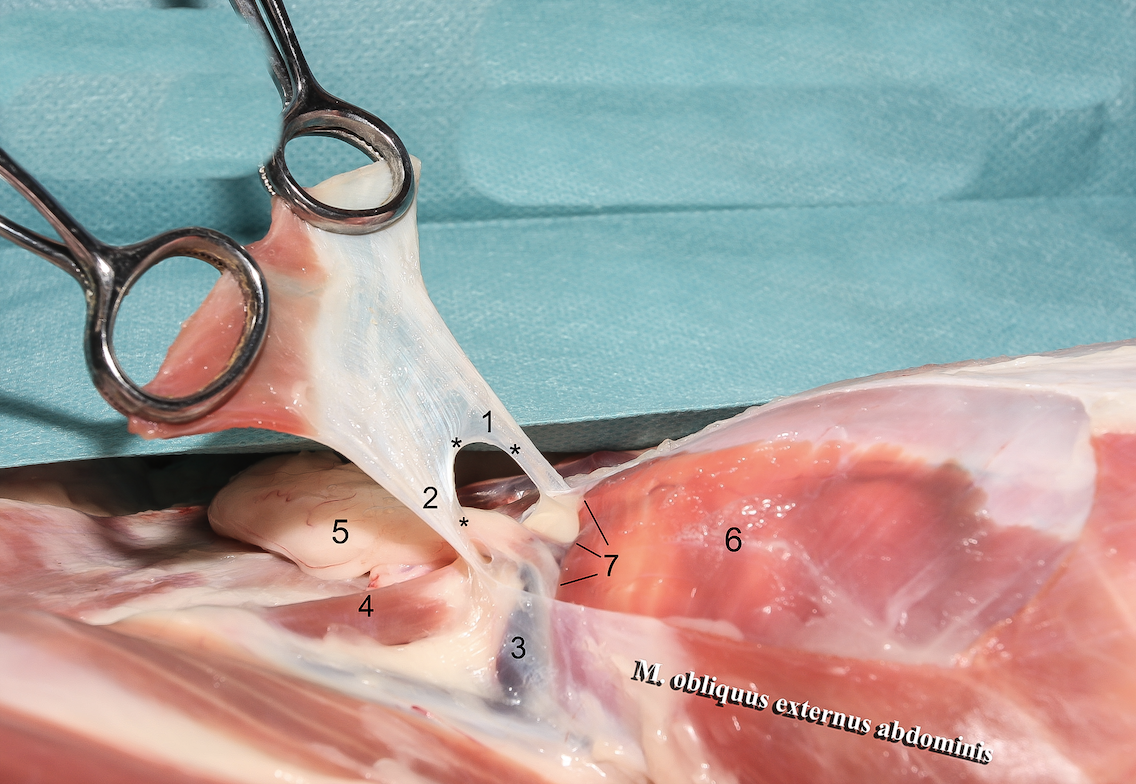

1

A

Crus mediale

6

Q

2

A

Crus laterale

7

Q

3

A

A./v. pudenda externa

8

Q

4

A

A./v. femoralis

9

Q

5

A

Processus vaginalis

10

Q

6

A

A./v. pudenda externa